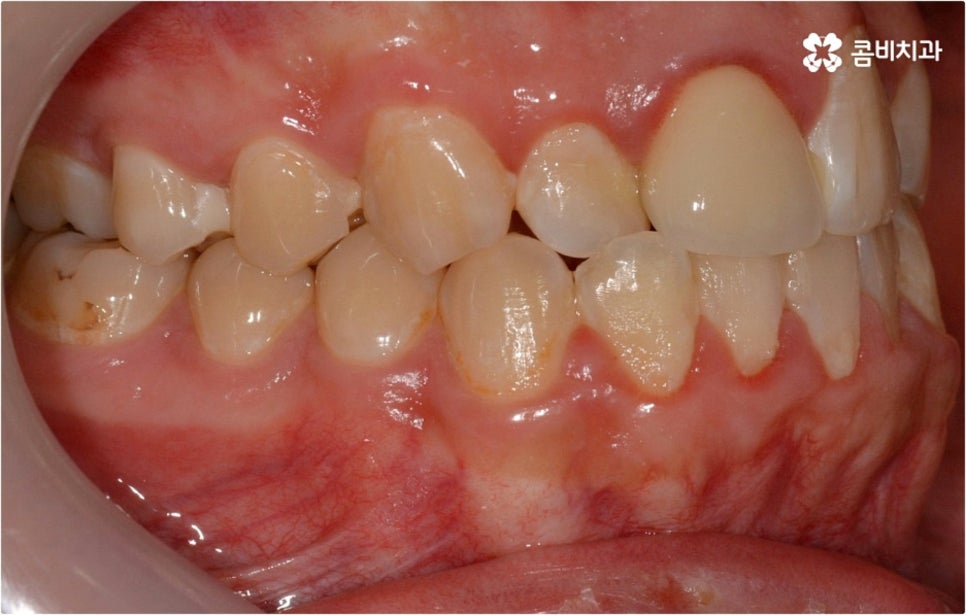

웃을 때 살짝 드러나는 덧니는 사람에 따라 매력 포인트로 느껴지는 경우도 있지만 구강 건강 측면에서 보면 치아와 치아가 겹쳐진 부분에 음식물 찌꺼기가 남아 치석이 쌓이기 쉽기 때문에 충치나 잇몸병이 더 자주 발생할 수 있으므로 주의하실 필요가 있습니다. 이와 같이 덧니는 옆 치아와 잇몸에까지 지속적으로 좋지...

출처 아카이브 열기웃을 때 살짝 드러나는 덧니는 사람에 따라 매력 포인트로 느껴지는 경우도 있지만 구강 건강 측면에서 보면 치아와 치아가 겹쳐진 부분에 음식물 찌꺼기가 남아 치석이 쌓이기 쉽기 때문에 충치나 잇몸병이 더 자주 발생할 수 있으므로 주의하실 필요가 있습니다. 이와 같이 덧니는 옆 치아와 잇몸에까지 지속적으로 좋지 않은 영향을 주기 때문에 개선해 주는 게 좋은데요, 특히 덧니의 개수가 많아 삐뚤빼뚤한 정도가 심하다면 교합이 잘 맞지 않아 씹기가 불편하거나 턱관절 압박, 통증 등을 유발할 수 있으며 나아가 안면비대칭으로 이어질 수 있기 때문에 방치하지 말고 될 수 있는대로 빨리 덧니교정 을 통해 이를 바로잡아 주시길 권유드리고 있습니다.

덧니교정 시 환자분들의 상황에 따라 치아 이동에 필요한 공간이 부족하지 않다면 비발치 교정이 가능한데요, 이런 경우 치아 사이를 살짝 갈아서 여유 공간을 만드는 치간 삭제 방법, 마지막 어금니를 후방으로 이동시키는 방법, 그리고 악궁 확장 장치를 사용해 치아 사이를 벌려주는 방법 등 다양한 방법으로 공간을 만들어 치열을 가지런하게 바로잡아 줄 수 있습니다. 이때 환자분들의 구강 상태, 즉 악궁 크기 대비 치아의 크기, 치아가 겹친 정도, 덧니의 위치와 개수 등을 자세하게 검진한 다음 치아가 이동할 충분한 공간이 확보되지 않는다면 발치 교정을 하게 될 거예요.

아마도 많은 분들이 치아를 뽑는다는 것에 대한 두려움을 가지고 있으시겠지만 그렇다고 해서 발치 교정이 필요한 케이스임에도 불구하고 치아를 뽑지 않고 진행을 하게 되면 치아 이동이 생각했던 것만큼 이루어지지 않기 때문에 결과에 따른 만족감이 떨어질 수 있어요. 특히 부정교합의 정도가 심각하고 골격적인 원인이 영향을 주고 있는 경우에는 발치 과정이 불가피 할 수 있으므로 의료진과 충분하게 상담을 하셔서 자신의 현재 상황에 따른 발치 교정의 필요성을 정확하게 이해하고 치료를 받으시길 권유드리고 있습니다.